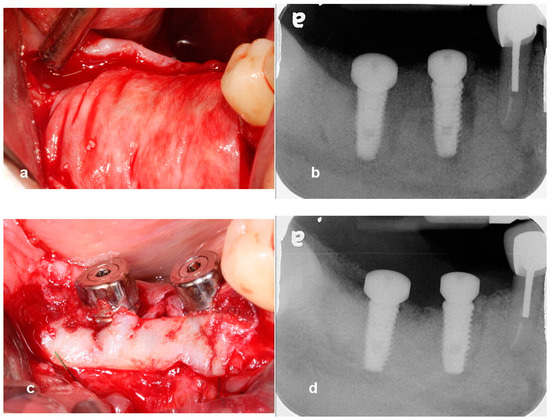

Utilization of Tenting Pole Abutments for the Reconstruction of Severely Resorbed Alveolar Bone: Technical Considerations and Case Series Reports

2. Case Presentations

- Woo, R.H.; Kim, H.G.; Kim, G.; Park, W.E.; Sohn, D.S. Simplified 3-dimensional ridge augmentation using a tenting abutment. Adv. Dent. Oral. Health 2020, 12, 185–205. [Google Scholar]

- Sohn, D.S. Reconstruction of three-dimensional alveolar ridge defects utilizing screws and implant abutments for the tent-pole grafting’ techniques. In Essential Techniques of Alveolar Bone Augmentation in Implant Dentistry, 2nd ed.; Tolstunov, L., Ed.; Wiley Blackwell: Hoboken, NJ, USA, 2023; pp. 404–418. [Google Scholar]